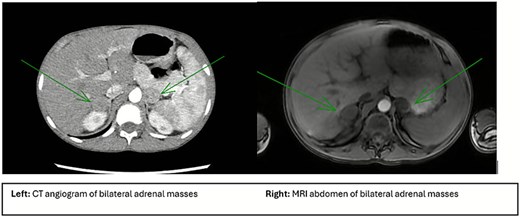

Imaging workup included a renal ultrasound which revealed bilaterally elevated renal artery velocities and medullary calcinosis consistent with medullary sponge kidney. A subsequent computed tomography (CT) angiogram which showed bilateral adrenal masses, no evidence of renal artery stenosis, and multiple enhancing lesions within the liver. Magnetic resonance imaging (MRI) of the abdomen for further characterization noted the right adrenal mass to be solid, homogenous, with restricted diffusion in the cortex measuring 2.4 × 2.4 × 2.3 cm; the left mass more heterogeneous, with small cystic components, restricted diffusion in the cortex but non-restrictive in the medulla measuring 2.0 × 2.3 × 2.0 cm. The liver nodules appeared to represent multiple areas of focal nodular hyperplasia (Fig. 1). The patient had a positron emission tomography (PET) scan which revealed moderate fluorodeoxyglucose (FDG) avidity in the left adrenal mass (SUV 3.2) and low FDG avidity in the right mass (SUV 2.1).

Imaging characteristics of adrenal pathology. Left image shows a CT abdomen and pelvis with arrows pointing to the bilateral adrenal masses measuring 2.5 × 2.0 cm on the right and 2.3 × 2.3 cm on the left. Right image shows an MRI of the abdomen and with arrows pointing to bilateral adrenal masses. Right mass is measured at 2.4 × 2.4 × 2.3 cm and is solid, homogeneous with a more dense capsule and moderate restricted diffusion. The left mass is measured at 2.0 × 2.3 × 2.0 cm and has a more heterogeneous appearance with small cystic components, cortex of the lesion with restricted diffusion.